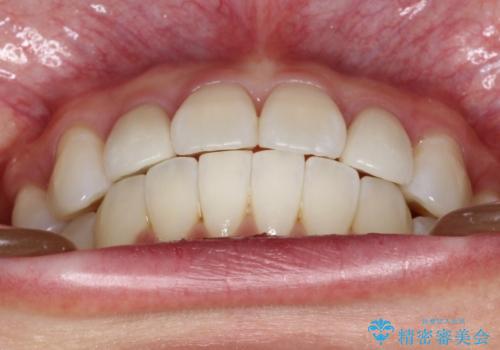

歯の大きさが通常と異なる場合は矯正治療で歯並びだけきれいにしても、整わないことがあります。

その場合はセラミックのかぶせ物を装着して歯の形を正常にすることで、さらに整った歯並びにすることができます。